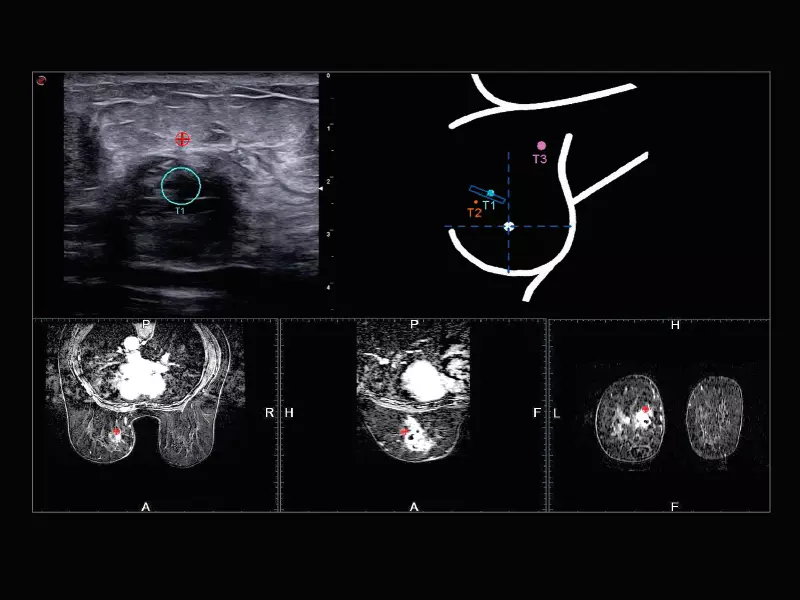

MyLab™X9 - Urology 01

MyLab™X9 - Urology 01

MyLab™X9 - Urology 02

MyLab™X9 - Urology 02

MyLab™X9 - Urology 03

MyLab™X9 - Urology 03

MyLab™X9 - Urology 04

MyLab™X9 - Urology 04

MyLab™X9 - Urology 05

MyLab™X9 - Urology 05

MyLab™X9 - Urology 06

MyLab™X9 - Urology 06